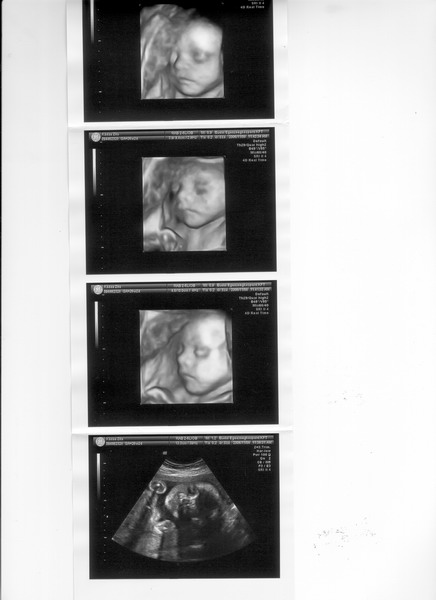

Az elsők a 19. héten, a második sorozat pedig a 30. héten készült.

Az elsők a 19. héten, a második sorozat pedig a 30. héten készült.